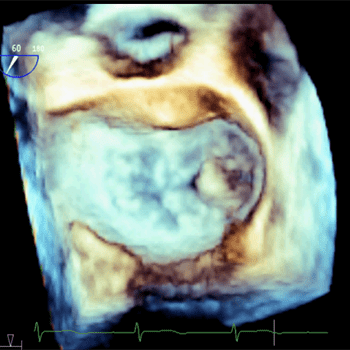

4. 当院の心エコー機械

入院施設、及び外来施設を併せて、心エコー機を計10台所有しています。最近ではEPIQ 7C(Philips社)という心エコー機に最新の経食道心エコー検査用プローブであるX8-2t(Philips社)を導入し、リアルタイム性に優れた明瞭な3次元イメージを活用しながら、構造的心疾患の診断、及び最先端の心臓弁膜症カテーテル治療に役立てています。

3Dイメージ

② 経食道心エコー

安静時の経胸壁心エコーにおいて、心臓の構造的な異常(例:僧帽弁逆流症などの心臓弁膜症、心房中隔欠損症などの先天性心疾患)が疑われる場合に実施されるのが経食道心エコーです。この検査は、胃カメラの要領で検査用のプローブを口から飲み込み、食道を介して心臓や血管の観察を行います。肺や肋骨などの障害となる構造物が少ないため、より明瞭な心臓や血管の観察が可能です。また、画像データから3次元画像も作ることができ、心臓や血管を3次元的に評価することもできます。食道内でのプローブを操作による苦痛を軽減するために、咽頭麻酔や鎮静剤などを使用しています。